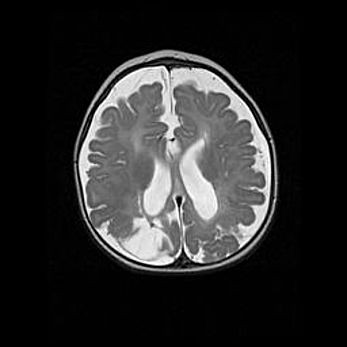

Множественные кисты обоих полушарий головного мозга, наибольшая из них в правой затылочной области. Ассиметричная атрофическая гидроцефалия.

Возраст: 7 месяцев

Вес: 5660 г

Пол: мужской

Окружность головы: 41,5 см

Срок гестации: 28-29 недель

Кисты головного мозга развиваются в результате многоочаговых некрозов вещества мозга и возникают вследствие перенесенной перинатальной инфекции, менингитов, энцефалитов, асфиксии, родовой травмы, расстройств мозгового кровообращения различного генеза. Образованию кист в веществе головного мозга плодов и новорожденных способствуют такие факторы, как высокое содержание в нем воды, недостаточная (или отсутствие) миелинизация и слабая астроглиальная реакция на повреждение.

Кисты могут сочетаться с гидроцефалией и другими поражениями головного мозга.